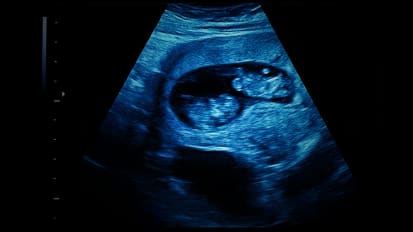

News Large Study Provides Reassurance That COVID-19 Vaccination Does Not Affect Fertility or Early Pregnancy